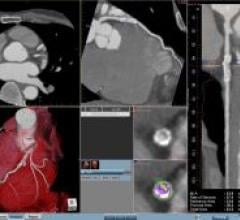

November 20, 2008 - TeraRecon Inc. released new innovations in the cardiovascular and vascular clinical applications for ...